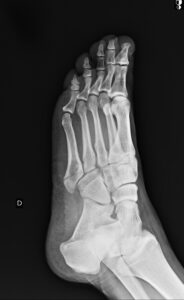

As duas imagens confirmaram a fratura da base do quinto metatarso.

O médico prescreveu anti-inflamatório de 12 em 12 horas por uma semana e o uso de uma bota imobilizadora de tornozelo e pé por trinta dias.